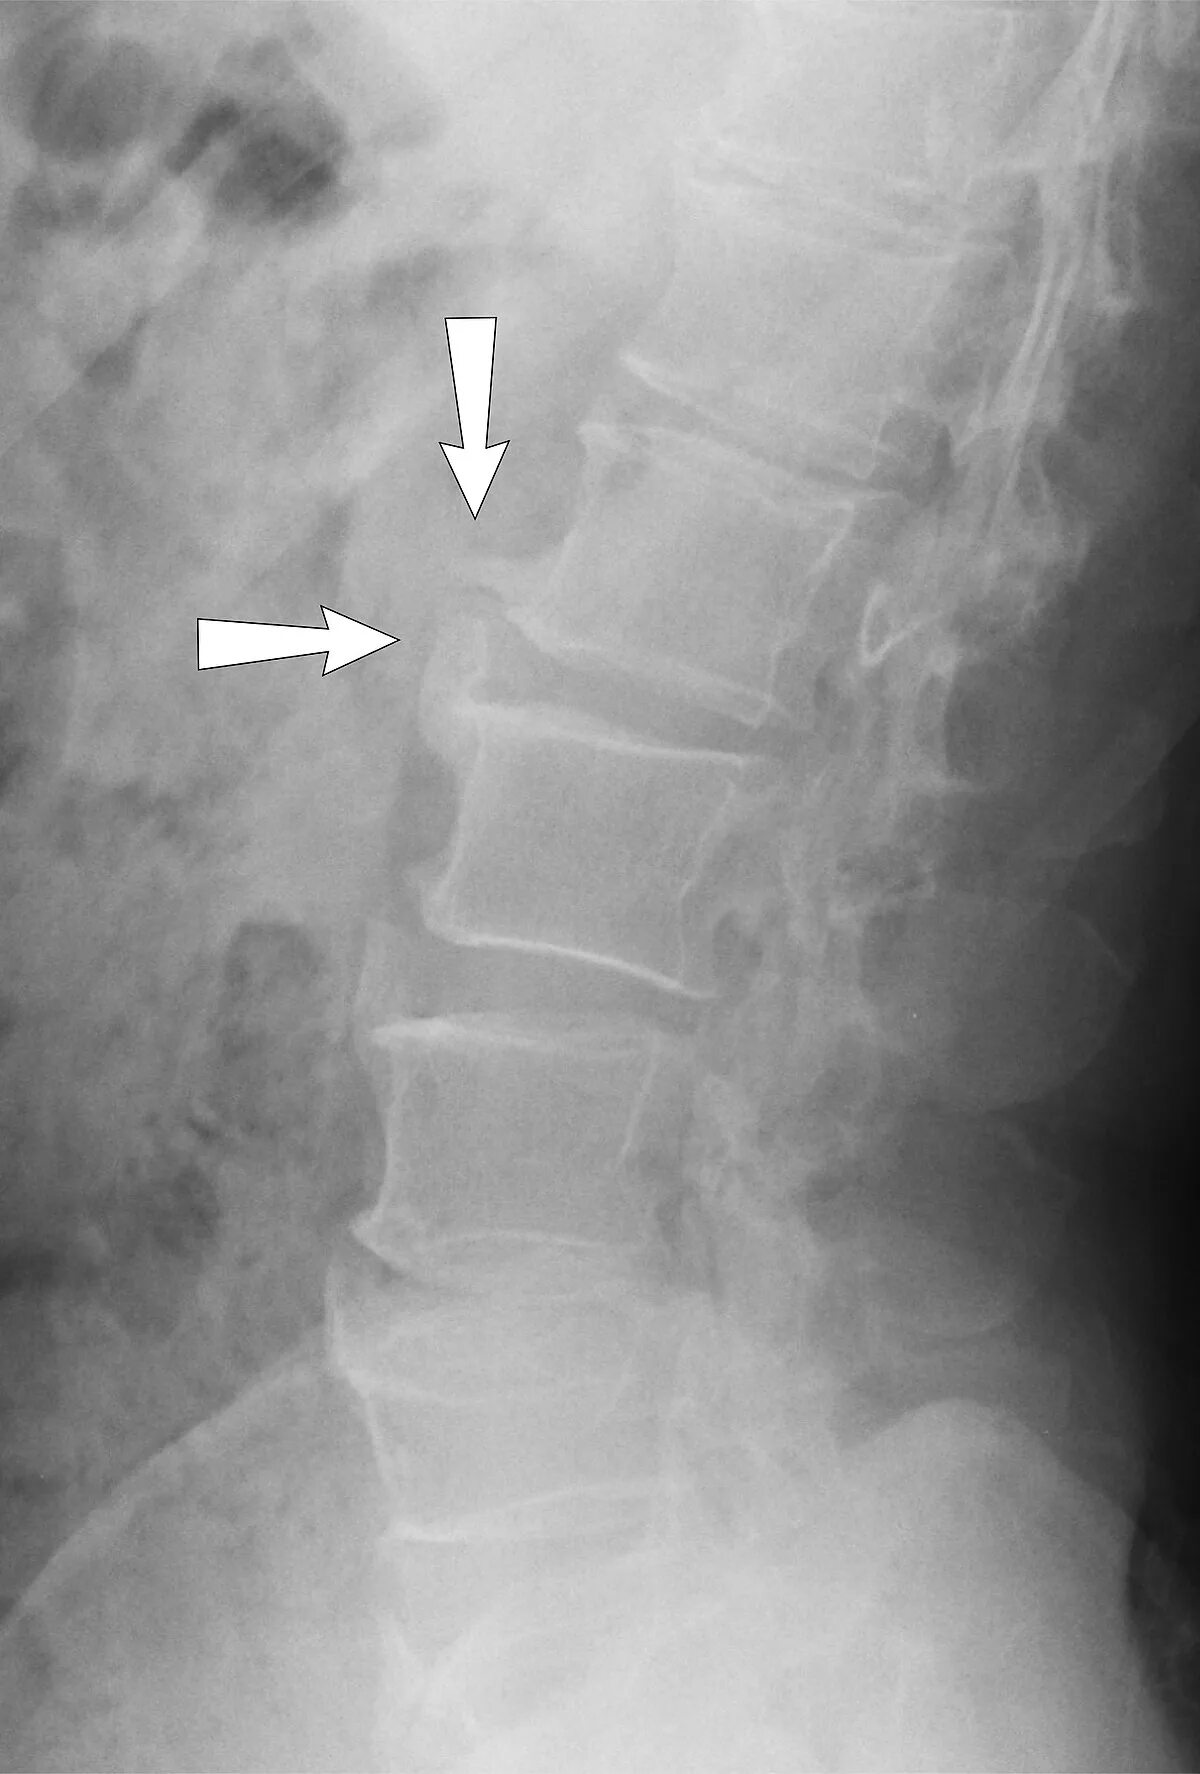

Как лечить спондилез поясничного отдела